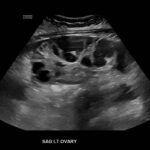

Ovarian hyperstimulation syndrome (OHSS) is a potentially life-threatening complication of assisted reproductive technology (ART). Here, we present the case report of a 30-year-old female undergoing infertility treatment who presented to the emergency department (ED) with nausea and vomiting, abdominal distention, and shortness of breath. On physical exam, she had notable ascites. Computed tomography (CT) of the abdomen and pelvis and pelvic ultrasound (US) revealed significant ascites and enlarged ovaries with multiple cysts. She was diagnosed with severe OHSS and admitted to obstetrics and gynecology (OBGYN) service for five days where she underwent intravenous (IV) hydration and paracentesis. This case report reviews the clinical presentation, categorization, management, and prevention of OHSS and provides examples of imaging findings consistent with the condition.